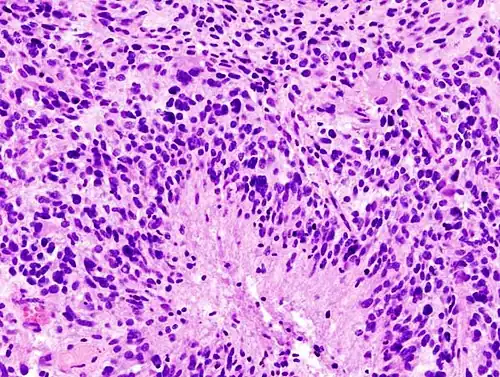

-

Histopathology of glioblastoma, showing high grade astrocytoma features of marked nuclear pleomorphism, multiple mitoses (one at white arrow) and multinucleated cells (one at black arrow), with cells having a patternless arrangement in a pink fibrillary background on H&E stain.

Lower magnification histopathology, showing necrosis surrounded by pseudopalisades of tumor cells, conferring a diagnosis of glioblastoma rather than anaplastic astrocytoma